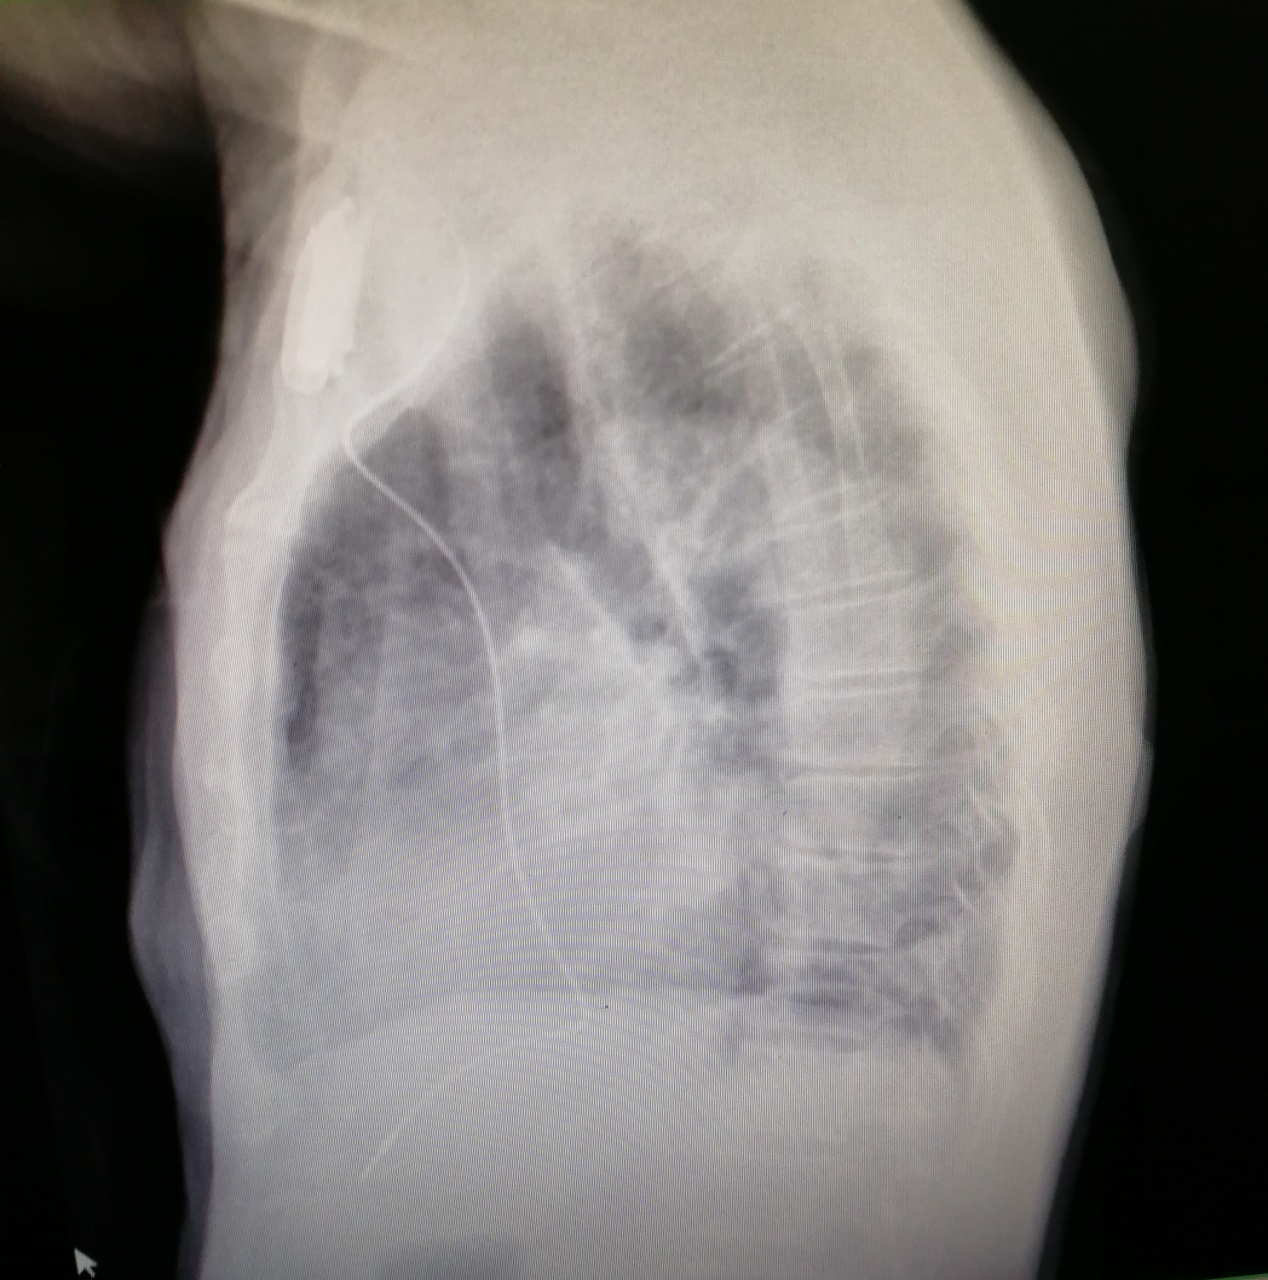

Alberto非常感谢中国医疗队对他的帮助,术后第二天查房时他对医生们说,现在感到特别轻松、头脑特别清醒,再也没有感受到头晕的痛苦了。术后胸部X片及心脏彩超均提示起搏器电极位置良好,没有气胸、心包积液等并发症,心电图也提升起搏功能良好。出院时得知他可以恢复正常生活,不需要再服用治疗心跳慢的药物时,Alberto显得特别高兴,因为他终于能像从前一样跟朋友们一起玩扑克牌了。他反复说着要感谢中国医疗队和中国医生,因为有他们的帮助他才得以重获新生。

术后胸片侧面